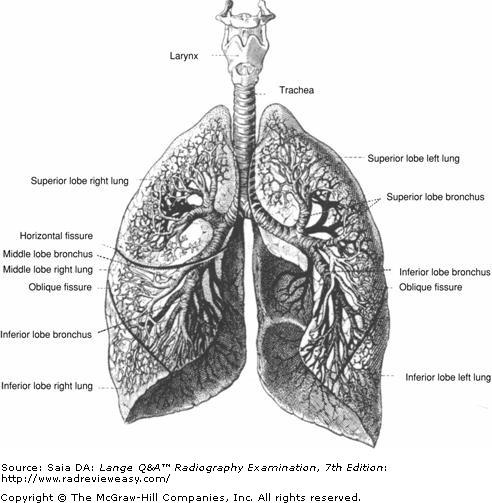

All of the following statements regarding respiratory structures are true except

A the right lung has two lobes.

-The trachea (windpipe) bifurcates into left and right mainstem bronchi, each entering its respective lung hilum. The left bronchus divides into two portions, one for each lobe of the left lung. The right bronchus divides into three portions, one for each lobe of the right lung (Fig. A). The lungs are conical in shape, consisting of upper pointed portions, termed the apices (plural of apex), and broad lower portions (orbases). The lungs are enclosed in a double-walled serous membrane called the pleura